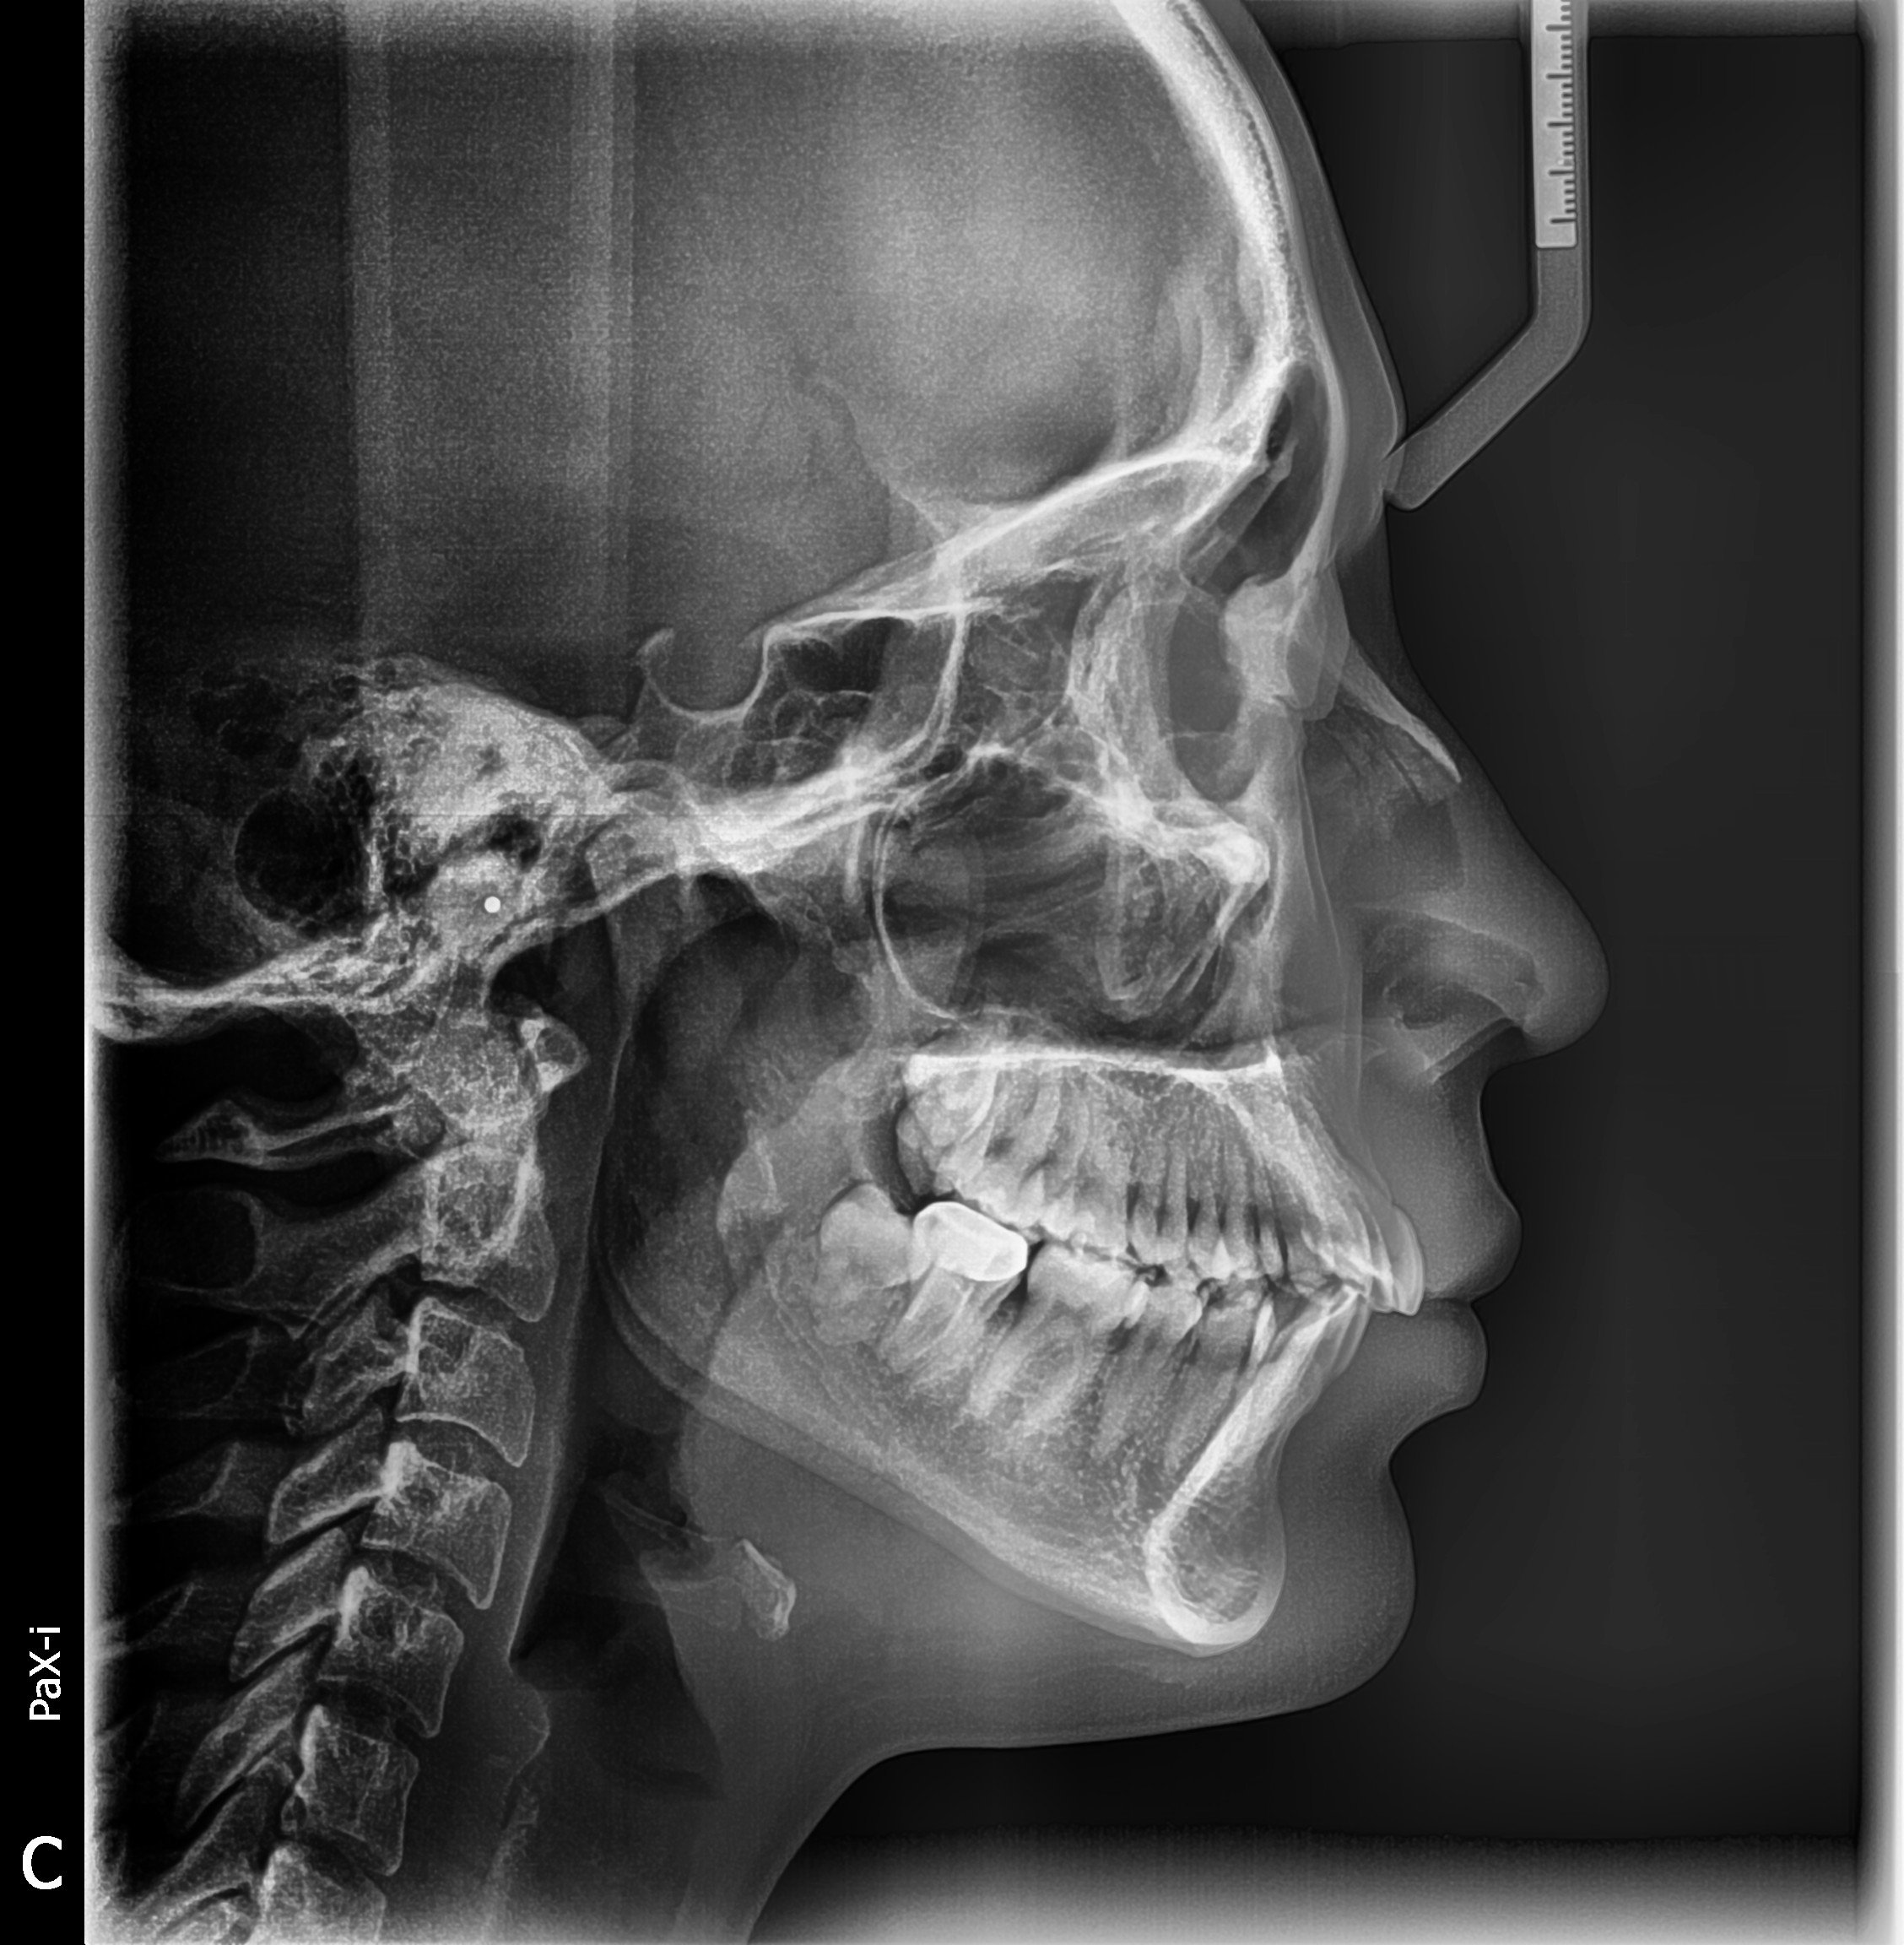

Radiografía Lateral de Cráneo

$250

La radiografía lateral de cráneo es un estudio especializado que captura una imagen de perfil de las estructuras óseas y dentales, ideal para análisis ortodóncico y planificación de tratamientos.